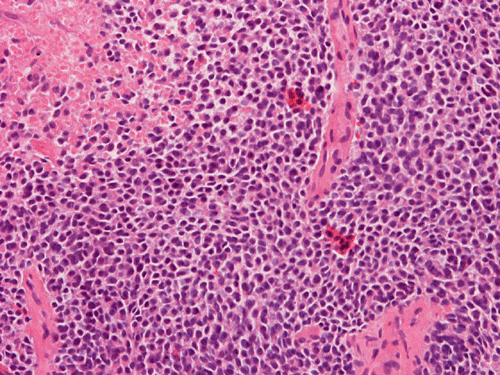

A. Hematoxylin & Eosin

B. Hematoxylin & Eosin

Pathology of the Case: Essentially, this is a small blue cell tumor with focal necrosis (Panel A and B). The nuclei are rather monotonous. Please note that the nuclei are slightly larger than most so-called small blue cell tumor such as small cell carcinoma of the lung. The tumor arrange in solid sheets without any pattern formation. There is a gap in between the cells. This is not uncommon in Ewing sarcoma. However, this pattern can also be seen in hematopoietic tumors such as lymphoma and plasmacytoma. In some areas, some of the tumor cells have a small rim of cytoplasm and some of these rims appear to be formed by fused minute bubbles (Arrow in Panel C). Results of speical stains, immunohistochemistry and molecular studies are as follow:

1. Hematoxylin and eosin stain, permanent section

Note the densely packed areas with hyperchromatic nuclei embedded in a background of nuclei with less hyperchromatic nuclei.